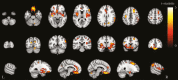

Results: The prevalence of cognitive impairment varied by up to 27% between methods used to define impairment (eg, 48% for HAND vs 21% for NMM in the CHARTER study). Associations between objective cognitive impairment and subjective cognitive complaints generally were weak. Physical and mental health summary scores (SF-36) were lowest for NMM-defined impairment ( P < .05).There were no differences in brain volumes or cortical thickness between participants with and without cognitive impairment defined using the HAND and GDS measures. In contrast, those identified with cognitive impairment by the NMM had reduced mean cortical thickness in both hemispheres ( P < .05), as well as smaller brain volumes ( P < .01). The associations with measures of white matter microstructure and brain-predicted age generally were weaker.

Conclusion: Different methods of defining cognitive impairment identify different people with varying symptomatology and measures of brain injury. Overall, NMM-defined impairment was associated with most neuroimaging abnormalities and poorer self-reported health status. This may be due to the statistical advantage of using a multivariate approach.